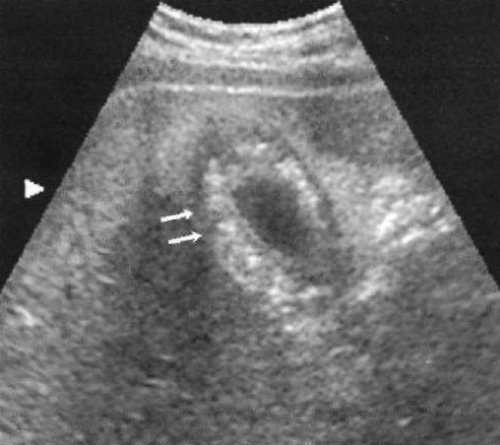

Симптом двойной дуговой тени (или триада СЭТ – стенка-эхо-тень) характеризуется наличием двух параллельно изогнутых эхогенных линий, которые разделены тонким анэхогенным пространством с дистальным звуковым затенением (фото 7).

Фото 7. Симптом двойной дуговой тени (триада СЭТ). На поперечном ультразвуковом изображении стрелкой указан передний отдел желчного пузыря с симптомом двойной дуговой тени, который характерен для сокращенного желчного пузыря с множественными желчными камнями

При триаде СЭТ проксимальная эхогенная линия соответствует стенке желчного пузыря, а более глубокая эхогенная линия – передней поверхности желчного камня, что вызывает образование звуковой тени. Симптом двойной дуговой тени выявляется при сокращении желчного пузыря, содержащего много желчных камней.